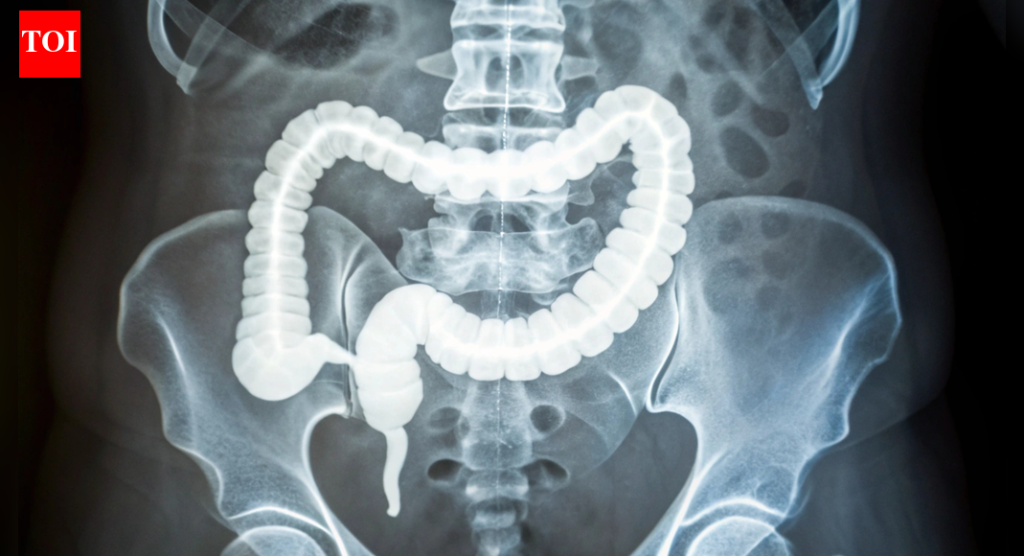

कोलोरेक्टल कॅन्सर आधी दिसल्यामुळे एक कडक कोलन अलार्म का वाढवत आहे: ते कसे ओळखावे

कोलोरेक्टल कॅन्सर हा वृद्धापकाळाचा आजार मानला जात असे, जो बहुतेक 50 नंतर आढळतो, परंतु गेल्या काही दशकांमध्ये, कोलोनोस्कोपीसारख्या व्यापक तपासणीमुळे त्या गटातील प्रकरणे-आणि मृत्यू कमी झाले आहेत. पण आता – 50 वर्षाच्या आधी होणारा कोलोरेक्टल कॅन्सर, जो 2020 पासून यूएस मधील सर्व निदानांपैकी 12% आहे. दर झपाट्याने वाढले आहेत, अद्याप एकही दोषी पूर्णपणे स्पष्ट केलेला नाही.बरेच लोक आधुनिक जीवनशैलीकडे निर्देश करतात: प्रक्रिया केलेले अन्न जड आहार, मध्यभागी अतिरिक्त पाउंड आणि पर्यावरणीय घटक जे कालांतराने आतडे चिडवतात. ही जुनाट सूज तात्काळ वेदना देत नाही परंतु शांतपणे तयार होते – संकटाचा टप्पा निश्चित करते. अंदाजानुसार 2030 पर्यंत ही संख्या दुप्पट होऊ शकते, विशेषत: त्यांच्या 20 ते 40 च्या दशकातील लोकांमध्ये, डॉक्टरांना तपासणी कधी सुरू करायची यावर पुनर्विचार करण्यास प्रवृत्त करते.

अलीकडील अभ्यासात कोलोरेक्टल कॅन्सर तरुण प्रौढांमध्ये का अधिक वेळा दिसून येत आहे यावर प्रकाश टाकला आहे, संभाव्य लवकर चेतावणी चिन्ह म्हणून कडक कोलनकडे निर्देश करते. अनेक वर्षांच्या निम्न-दर्जाच्या जळजळांमुळे चाललेले- हे ऊतक कडक होणे ट्यूमर पकडण्यासाठी आणि जलद वाढण्यासाठी योग्य वादळ निर्माण करते असे दिसते. संशोधनामागील तज्ञांना आशा आहे की हे निष्कर्ष 50 वर्षांखालील लोकांसाठी तयार केलेल्या चांगल्या तपासणी आणि उपचारांसाठी दरवाजे उघडतील.सुरुवातीचे नमुने वेगळे होते: एकूणच अधिक कठोर. सखोल खोदल्यावर, टीमला कोलेजनचे जाड, लांब पट्टे आढळले, प्रथिने जे डाग पडताना तयार होतात. हे कोलेजन अधिक परिपक्व आणि सुबकपणे संरेखित होते, वारंवार जळजळ होण्याची चिन्हे त्याची छाप सोडतात. जीन चाचण्यांनी याची पुष्टी केली, कोलेजन प्रक्रियेसाठी वाढलेली क्रिया, नवीन रक्तवाहिन्यांची वाढ-आणि तरुण रुग्णांच्या ऊतींमध्ये चालू असलेली रोगप्रतिकारक प्रतिक्रिया दर्शविते.

येथे ते आकर्षक होते. आतड्यात तीव्र चिडचिड झाल्यामुळे स्तनाच्या किंवा स्वादुपिंडाच्या कर्करोगाप्रमाणेच कोलनच्या भिंती घट्ट होतात. पेशी याकडे दुर्लक्ष करत नाहीत; त्यांना मेकॅनोट्रांसडक्शन नावाच्या प्रक्रियेद्वारे पिळणे जाणवते. मेकॅनिकल स्ट्रेस फ्लिप पेशींच्या आत स्विच करतात, जैवरासायनिक सिग्नल स्पार्क करतात जे त्यांना विभाजित आणि पसरण्यास सांगतात.मुद्दा सिद्ध करण्यासाठी, शास्त्रज्ञांनी पृष्ठभागावर कोलोरेक्टल कर्करोगाच्या पेशी वाढवल्या आणि वेगवेगळ्या कडकपणाच्या पातळीची नक्कल केली. कडक असलेल्यांवर, पेशी जलद गुणाकार करतात. त्यांनी अगदी रूग्णांच्या पेशींमधून 3D ऑर्गनॉइड्स—मिनी ट्यूमर मॉडेल्स—बनवले, आणि जे कडक पायावर आहेत ते अधिक मोठे आणि जलद झाले. हे सूचित करते की कठोर वातावरण केवळ कर्करोग वाढू देत नाही; हे सामान्य पेशींना प्रथमतः घातकतेकडे ढकलू शकते.